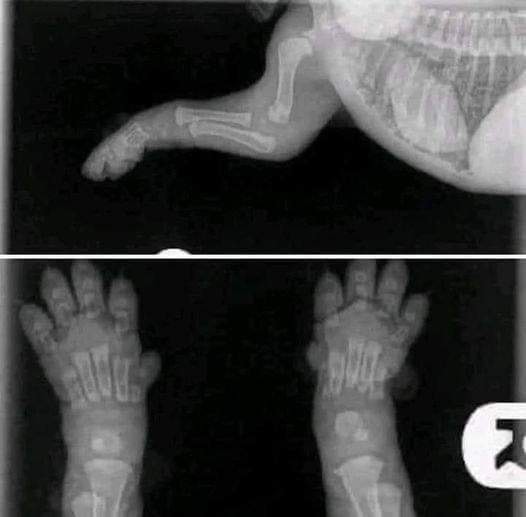

This is something everyone should see. This xray is of a 2 week old puppy.

When you get your 8/10 week old puppies, please keep this image in mind. Their bones do not even touch yet. They plod around so cutely with big floppy paws and wobbly movement because their joints are entirely made up of muscle, tendons, ligaments with skin covering. Nothing is fitting tightly together or has a true socket yet.

When you run them excessively or don’t restrict their exercise to stop them from overdoing it during this period you don’t give them a chance to grow properly. Every big jump or excited bouncing run causes impacts between the bones. In reasonable amounts this is not problematic and is the normal wear and tear that every animal will engage in.